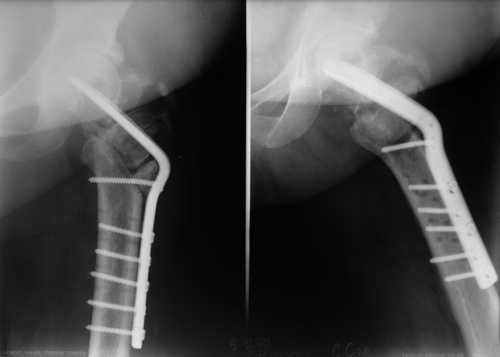

1. судя по снимкам, не складывается впечатление, что речь идет о ложном суставе шейки бедра – скорее, оскольчатом трохантерном переломе

2. фиксация проксимального отдела бедра неоптимальна ( blade plate проходит через верхнюю , наиболее порозную часть шейки бедра). Вряд ли 6 (!) шурупов в дистальный отдел бедра добавляют прочности данному импланту.

по-моему, остеотомия выполнена немного выше оптимального уровня.

Да, 2-3 винтов было бы достаточно. Реально работают самый нижний и самый верхний винты.

blade в нашем случае явно в верхней, наиболее порозной части шейки и головки ( в отличие от описанного в статье), так что риск коллапса и "прорезания" лезвия в сустав при ранней нагрузке крайне велик

"blade в нашем случае явно в верхней, наиболее порозной части шейки и головки". В "нашем" случае blade установлено в крайний нижний сегмент головки, т.е. в самый прочный и не порозный. Это можно уведеть сравнив первичные снимки представленные 16.11.08 и косвенно по просветлению в головке (место бывшего расположения динамического винта) располающемуся ВЫШЕ клинка.

ОК, в центре ( ну уж никак не в наиболее нижнем сегменте :) головки и в верхней части шейки ( честно говоря, у меня складывается ощущение, лезвие входит в шейку либо сверху, а не через перелом, либо по верхнему кортикалу, но настаивать не буду - разрешение снимков недостаточно, чтоб говорить об этом с уверенностью)

Сказать, что blade plate безнадёжно устарел, наверное неправильно, но то, что в данной ситуации это наиболее удачная методика - однозначно нет. Учитывая, что лезвие клинка вколочено в отломки говорить об адекватной стабилизации не приходится. Количество винтов в дистальном отделе, действительно не категорично. В приблизительно подобной ситуации нами применён был имплант с угловой стабильностью, дополнительно с компрессирующими винтами в шейку. Для заполнения дефектов между отломками использовали "КоллапАн", костные чипсы, Chronos. По рентгенограммам ранней нагрузки я бы давать не стал, случай не рядовой и достаточно сложный. Но ничего не предпринимать в такой ситуации тоже неправильно. То что Вам прочят проблемы, ах-оставьте, у кого их не было. Динамический контроль, работа с пациентом, неплохо добавить миакальцик (назальный спрей). Дерзайте, дорогу осилит идущий.